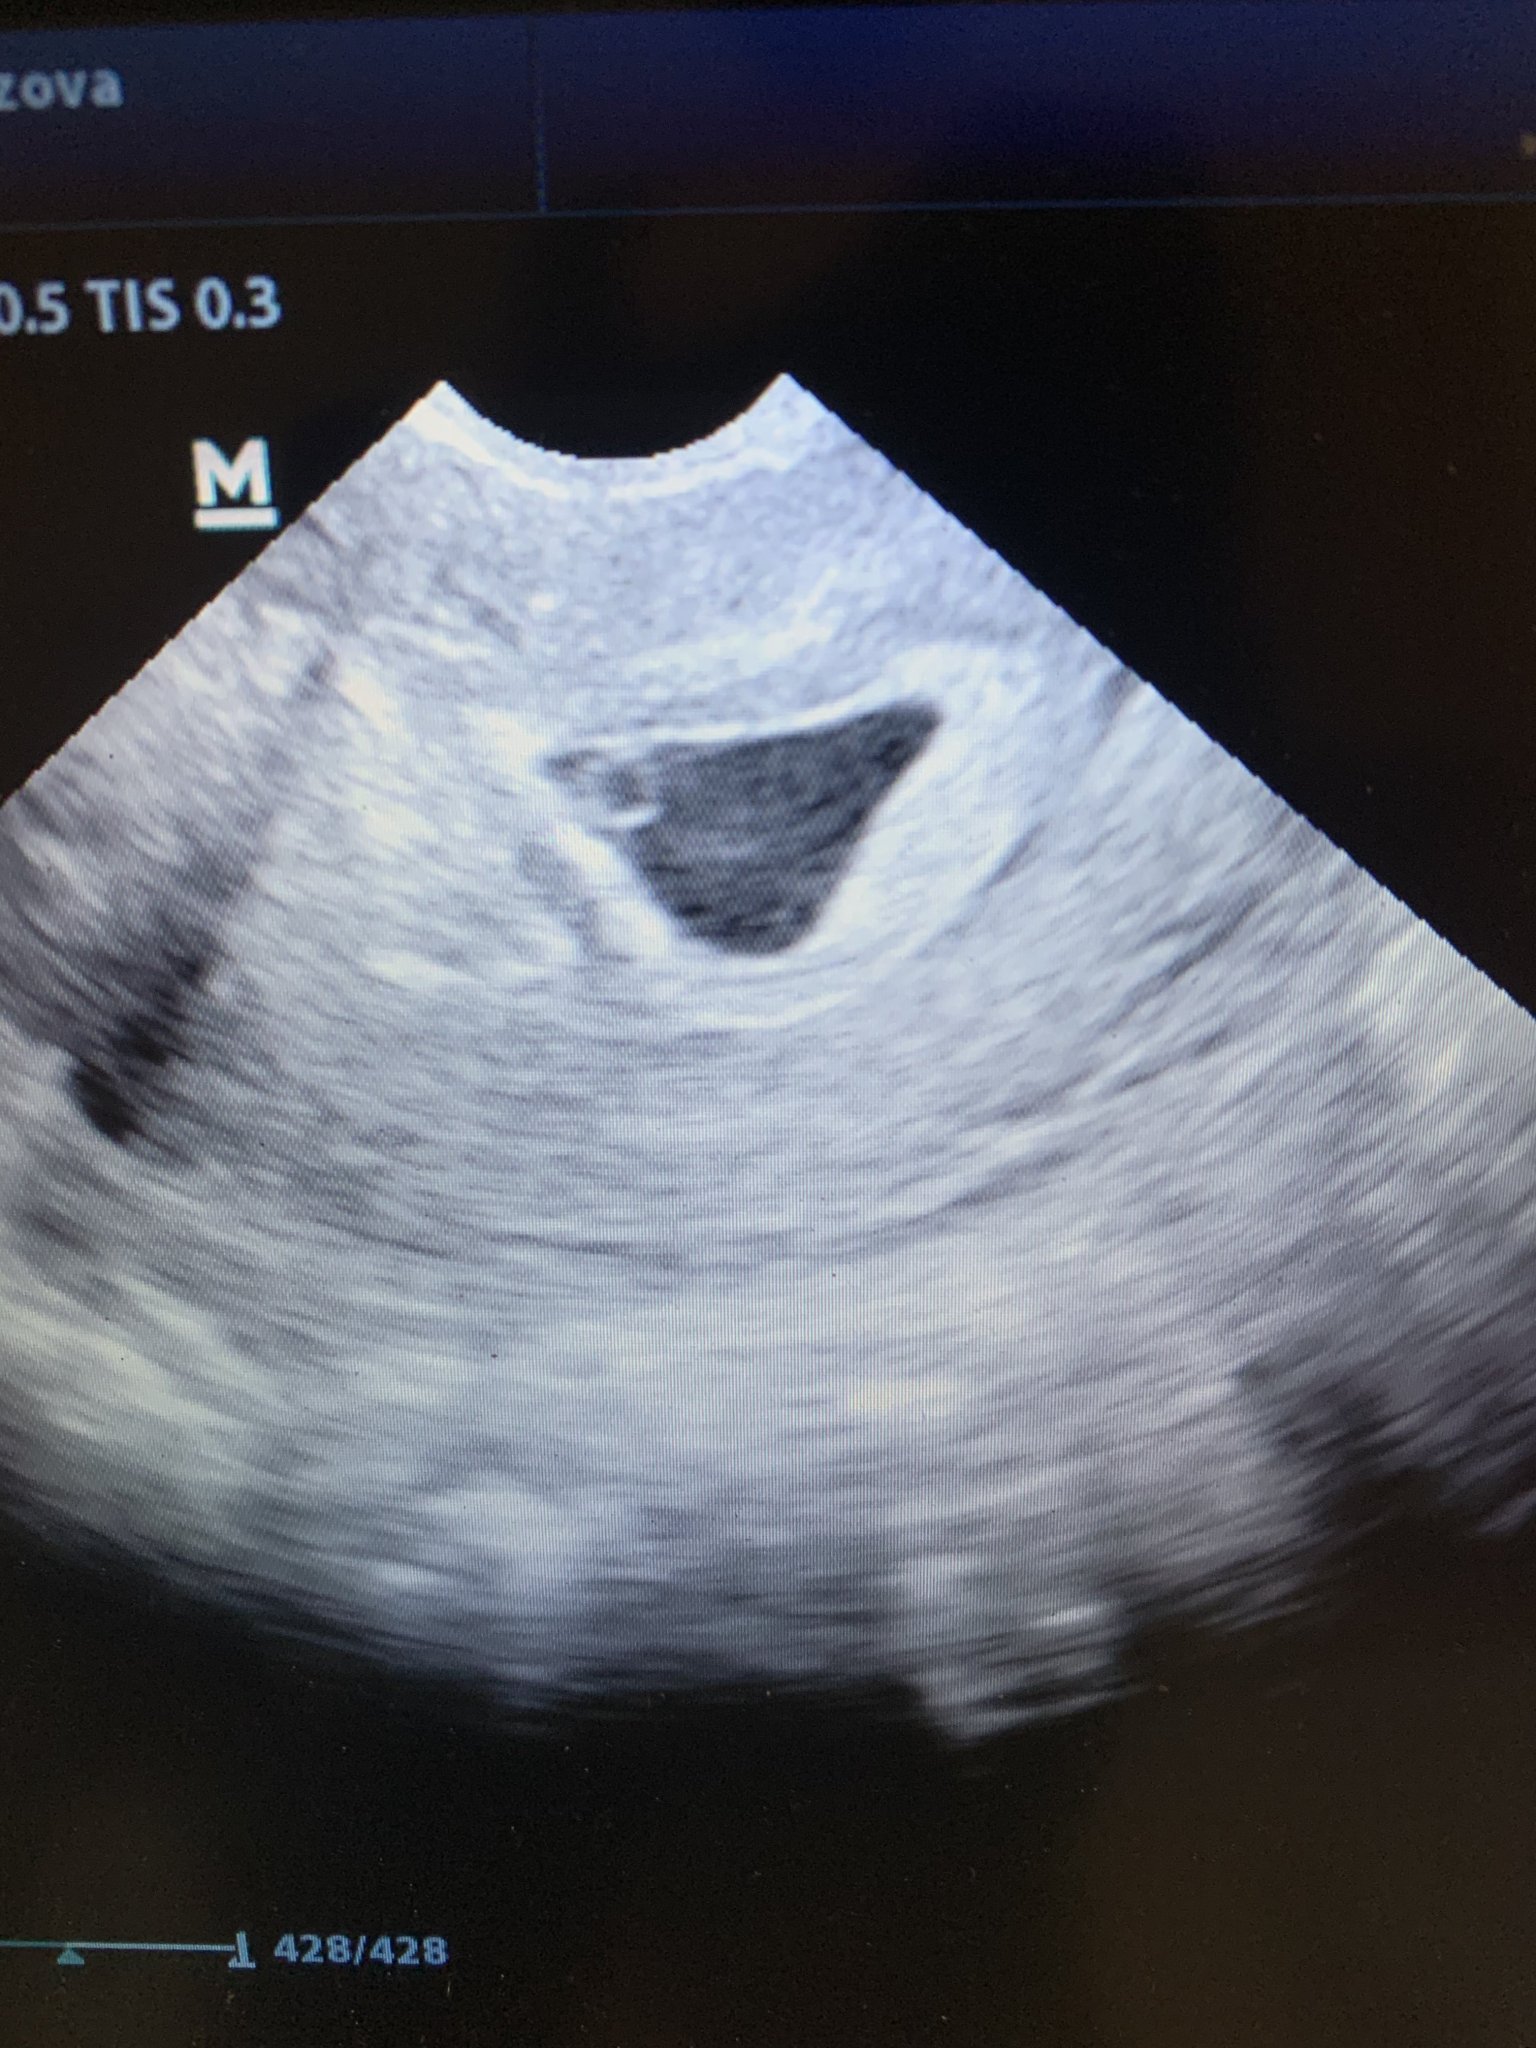

Здравейте! Прикачвам снимка от днешен видеозон. Притеснителна ли е формата на плодния сак, по изчисления на АГ съм между 6 и 7г.с., според мен точно в 6 /тъй като цикъла ми е на 34 дни и овулацията ми е болезнена/, та по нейни думи е притеснителна формата на плодния сак, ембрион “НЯМА”, само жълтъчно мехурче, което нищо не значело, но било добре че го има. Има ли повод за притеснение? Да ходя ли на второ мнение? Тъй като съм с киста която трябва да се наблюдава през няколко дни, не знам прекаленото гледане на видеозона дали е полезно, да изчакам ли следващ преглед след 10 дни или да тичам веднага при друг АГ? ПООМОООЩ